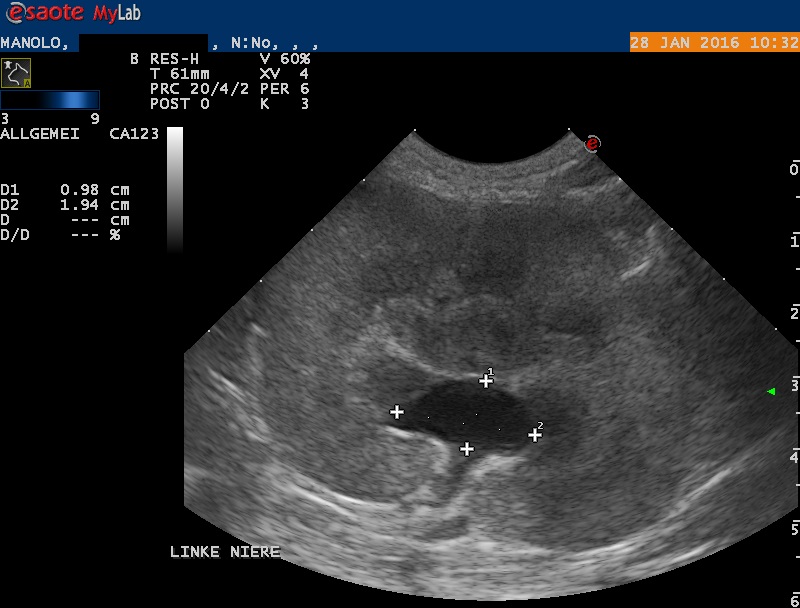

Der Bauch von Manolo wird mittels Ultraschall untersucht: Die rechte Niere erscheint klein und weist eine veränderte Architektur auf. Die linke Niere ist deutlich vergrössert; das Nierenbecken ist erweitert, und auch der ableitende Harnleiter ist deutlich erweitert. Im Nierenbecken findet sich ein kleiner Nierenstein von ca 4x2x2 mm Grösse. Mittels steriler Punktion wird Urin aus der Harnblase entnommen - im Urin befinden sich grosse Mengen rote und weisse Blutkörperchen sowie Baktieren, auch ist der Harn wenig konzentriert.

Die Erweiterung des Beckens und des Harnleiters (Ureter) der linken Niere weisen auf eine Blockade des Harnleiters hin, welcher den Urin von der Niere in die Blase transportieren sollte. Durch die Blockade wird Urin gestaut und das Nierenbecken und der vor der Blockade liegende Teil des Ureters quasi "aufgeblasen". Die Folge ist eine Funktionsstörung der Niere, wodurch sich die Nierenwerte im Blut erhöhen. Die beobachteten Veränderungen der rechten Niere könnten darauf hinweisen, dass auch dieses Organ in der Vergangenheit eine ähnliche Schädigung erlitten hat - dadurch, dass die linke (damals gesunde) Niere noch normal funktionierte, wurde diese Schädigung möglicherweise nicht bemerkt.

Harnleiterblockaden sind bei Katze nicht allzu selten. In vielen Fällen ist ein kleiner Nierenstein, welcher aus dem Nierenbecken abgegangen und im Harnleiter stecken geblieben ist, die Ursache des Problems. Bei Manolo wurde allerdings kein solcher Stein gefunden (obwohl im Ultraschall ein kleiner Nierenbeckenstein entdeckt wurde) - offenbar bewirkte eine möglicherweise infektionsbedingte Schwellung des Harnleiters die Blockade.

In manchen Fällen präsentiert sich das Problem als "big kidney/little kidney"-Problem: Die eine, kürzlich beschädigte Niere ist stark vergrössert, die andere, früher vom selben Problem betroffenen Niere infolge einer Narbenbildung verkleinert.